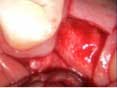

A 53-year-old female with a medical history of hypothyroidism, seasonal allergies, and asthma taking Synthroid and Singula presented to my office with pain in No. 3, failed root canal therapy, and a fracture. The tooth was deemed hopeless and extraction and implant placement was treatment planned. Under local anesthesia, tooth No. 3 was sectioned into three pieces and extracted. The sockets were debrided, filled with gel foam, and closed with chromic gut sutures. Healing was uneventful. The patient did not return for two years for follow-up. A CT scan was taken, which confirmed that approximately5 mm of bone remained below the floor of the sinus. After reviewing the options with the patient, a treatment plan of an internal sinus lift (osteotome), bone graft, platelet-rich fibrin (PRF) and simultaneous implant placement was agreed upon. Under local anesthesia, a full thickness flap with two vertical releasing incisions was performed at tooth No. 3 site. A trephine bur was used to a depth of 4 mm. An osteotome was then employed to infracture the bone core, which remained attached to the Schneiderman membrane. A bone graft consisting of DFDBA, anorganic bovine bone, and PRF was used in the osteotomy to increase the vertical bone height using sequential osteotomes. After sufficient elevation, a 7x9 tapered implant was placed on low speed to 50% of the implant depth. The remaining placement of implant was done with a hand torque on 50 ncm to allow for further expansion of the alveolar housing. A healing abutment was placed using the principles of platform switching. Healing was uneventful, and integration was successful.

Case 1: Implant and osteotome bone graft through the socket with Southern Implant